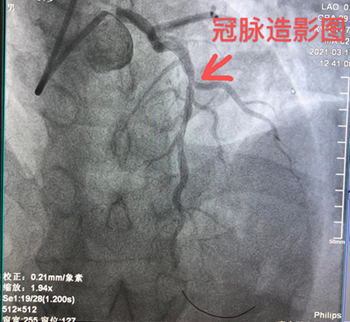

【新技术】我院心内科开展测量冠脉血流储备分数(FFR)技术

近日,我院心内科为一位心绞痛患者行冠脉血流储备分数(FFR)检查,该患者经冠脉造影检查提示最严重的病变在前降支中段,狭窄约75%,属临界病变。从冠脉造影来说,可植入支架,亦可不植入支架,在无开展功能学检查的情况下,全凭医生的经验判断。

为进一步评估是否存在心肌缺血及是否需要植入支架PCI治疗,心内科刘扬主任医师及廖远雄副主任医师为患者进行FFR的测量操作,最终为该患者测量的结果为0.81,该结果提示心肌缺血的可能性小,遂避免了植入冠脉支架介入治疗。